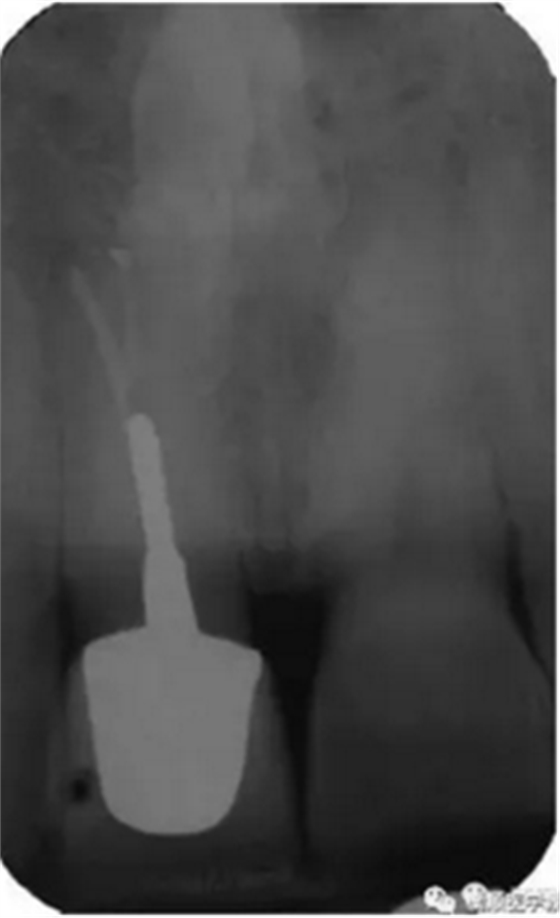

基于臨床檢查和X線片顯示,診斷為右上頜中切牙根尖周炎伴額外牙。治療計劃是先行患牙的根管治療,制作臨時義齒,最后制作樁核冠。應(yīng)用橡皮樟和顯微根管技術(shù),利用ProTaper旋轉(zhuǎn)銼配合使用 Hedstrom 銼和桉葉油,將根管內(nèi)充填物取出,觀察X線片可見根尖三分之一處主根管一分為二,確定另一根管的工作長度,兩根管同行常規(guī)根管治療,充填后X線片顯示根管充填良好。樁核冠修復(fù)1年后,患牙無疼痛,影像檢查發(fā)現(xiàn)根尖顯影正常,根尖疾病治愈。

圖3. 樁核冠修復(fù)1年后患牙根尖周顯影